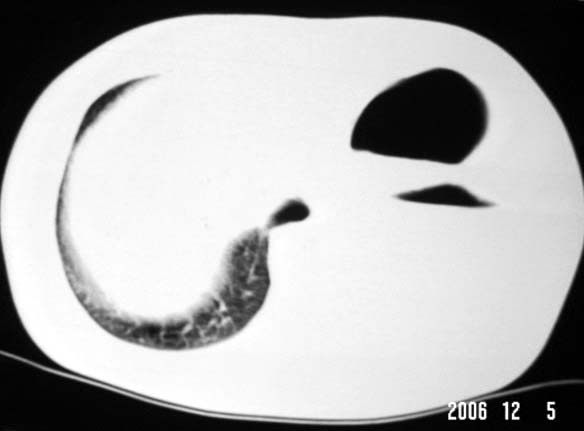

标题: CT5517:女性、24岁,反复胸痛、气促不能平卧半月。 [打印本页]

标题: CT5517:女性、24岁,反复胸痛、气促不能平卧半月。

左肺可见二个含气或液气的囊状影,左肺段支气管、左肺动脉显示不清,纵隔右移,考虑:左肺支气管肺囊肿,左肺发育不良,纵隔疝。

左侧气液腔与胃腔影相连,考虑膈疝。钡餐检查有助于诊断。

我看这是膈疝,在纵隔窗第六\\七幅图像上可见胃粘膜影,再者可见两个腔影,这在液气胸是不会有的.

支持膈疝,纵隔窗内可见消化道的内容物。

“反复胸痛、气促不能平卧半月”。+影像学表现=膈疝